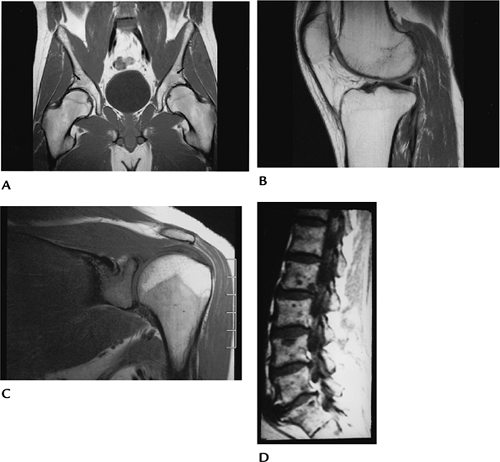

243ce74d43331f01eacdb455dfafedfc.gif

图-1骨髓模式。骨盆、膝关节、肩关节和脊柱T1WI像。在成人中,骨盆的骨髓主要为脂肪性骨髓,除了髋臼区(箭头)有小面积的红骨髓。年长成人膝关节也有高信号的脂肪性骨髓。20岁患者肩关节骨骺高信号脂肪性骨髓,肱骨骨干和肩胛盂中有红骨髓。脊柱显示主要为黄骨髓,但由于多发转移,存在低信号区。